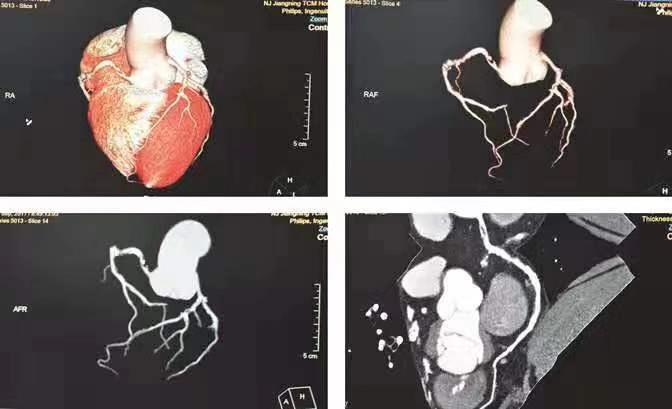

1.冠状动脉血管CT成像(CTA)

冠脉CT是经外周静脉注射造影剂后对冠状动脉行CT检查,将影像数据进行重建后处理,显示冠脉主要分支走行、狭窄程度及心脏形态的一种检查方法,其作为一种无创诊断冠状动脉病变的方法,因在疾病诊断方面近于冠脉造影检查,从而更受患者及临床认可。